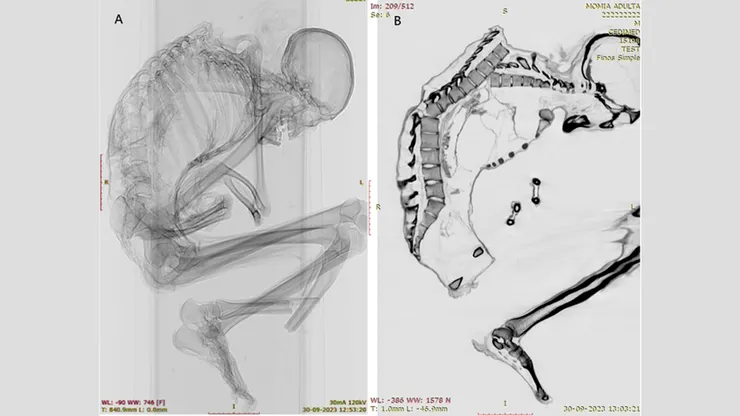

在[2025年]12月15日發表於《國際骨骼考古學期刊(International Journal of Osteoarchaeology)》上一項研究中,智利聖地亞哥(Santiago)國家自然歷史博物館(National Museum of Natural History)考古學家卡塔琳娜‧莫拉萊斯(Catalina Morales)與法蘭西斯科‧加里多(Francisco Garrido)運用電腦斷層掃描與X光成像技術,揭開可能這名男子致命創傷的複雜細節。

這名男子的上脊椎有多處未癒合的骨折。此外,他的肋骨、肩胛骨與鎖骨也有骨折,這表明他的上背部「大面積受到鈍力衝擊」,莫拉萊斯與加里多在研究中寫道,他的「左上胸承受了大部分衝擊力」。衝擊導致他的幾節椎骨移位,並造成肋骨塌陷。

此外,研究人員還在他脊椎底部附近的一節椎骨上發現一處骨折,這很可能是最初上背部受傷造成的。研究人員寫道,上脊椎與下脊椎的損傷「通常都會導致嚴重的脊髓損傷與高死亡率」。

但經檢查,該男子的頭骨、頸部與手臂均未發現任何損傷,顯示撞擊發生時,男子頭部朝下。他當時可能正在採礦,或試圖用手臂保護頭部,但被從上方墜落的重物擊中。研究人員指出,這種類型的損傷常見於地震傷者以及林業、建築和採礦等行業的工傷事故。